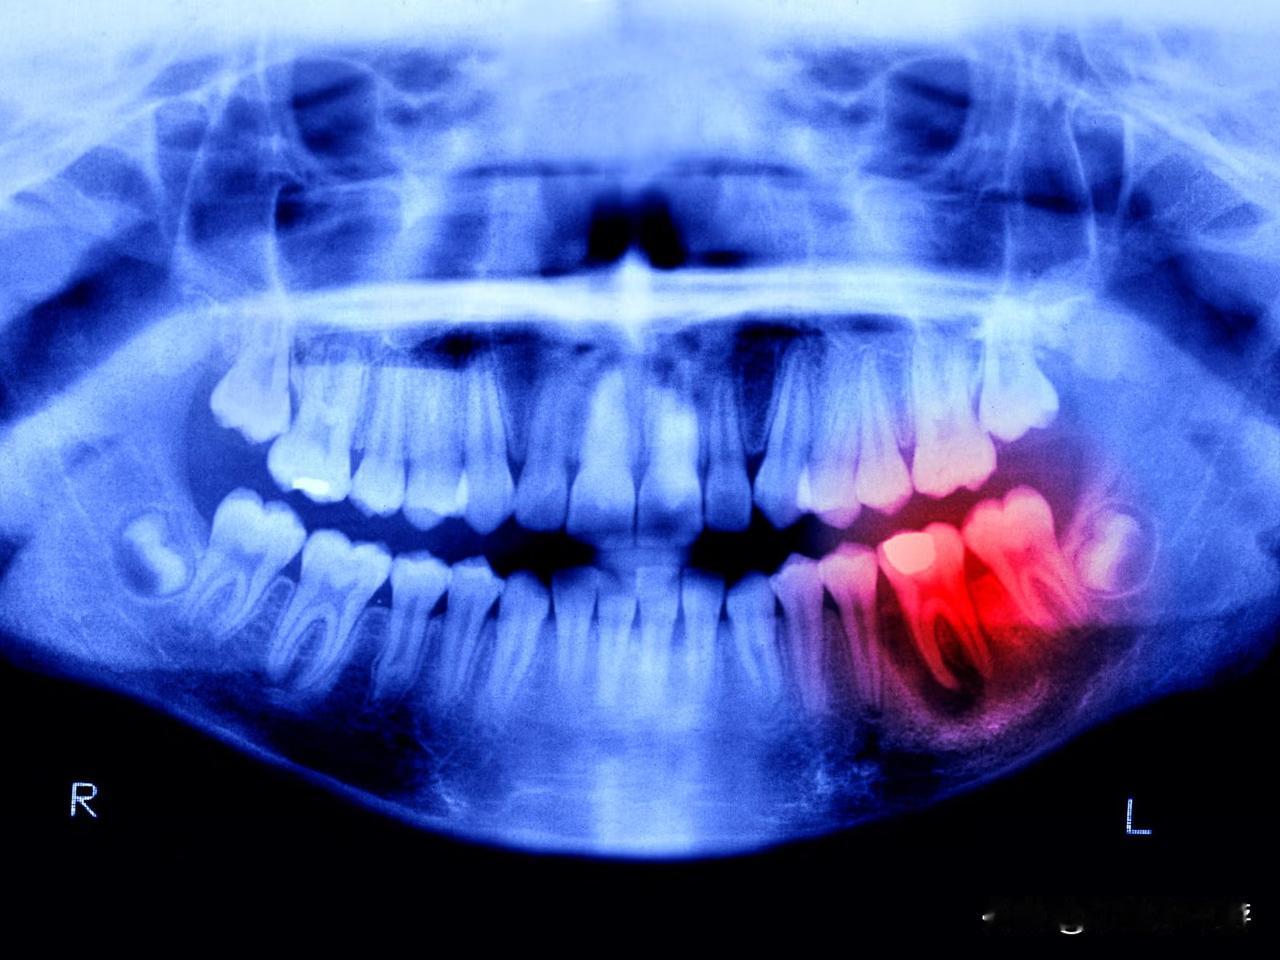

日本“牙齿再生药物”已开启人体试验,目标是在2030年实现上市。 日本科学家正在推动一项仿若出自科幻电影的重大突破——让人类重新长出牙齿。这款由大阪北野医院和京都大学联合研发的“牙齿再生药”,于2024年9月正式启动人体临床试验。 众所周知,骨头断裂后能够自行愈合,然而牙齿一旦脱落便无法自然再生。这是因为人体内存在一种名为USAG - 1的基因,它会抑制牙齿的生长。研究团队发现,通过药物来阻断这种基因的相互作用,就能够解除牙齿“生长的禁锢”。此前这种疗法已在老鼠和雪貂身上验证成功,不仅安全性良好,还能让它们长出完整的新牙。 当前处于临床第一阶段,主要选取了30名缺牙的成年男性作为试验对象,重点在于测试药物的安全性。若一切进展顺利,下一阶段将针对2至7岁先天性缺牙的儿童展开治疗。 团队负责人高桥克表示,计划在2030年左右将该药物投放市场。尽管初期主要针对先天性缺牙患者,但未来有望推广到所有因蛀牙或意外事故导致牙齿脱落的普通人群。这预示着,困扰人类许久的假牙和种植牙时代,或许在几年后就会宣告结束。